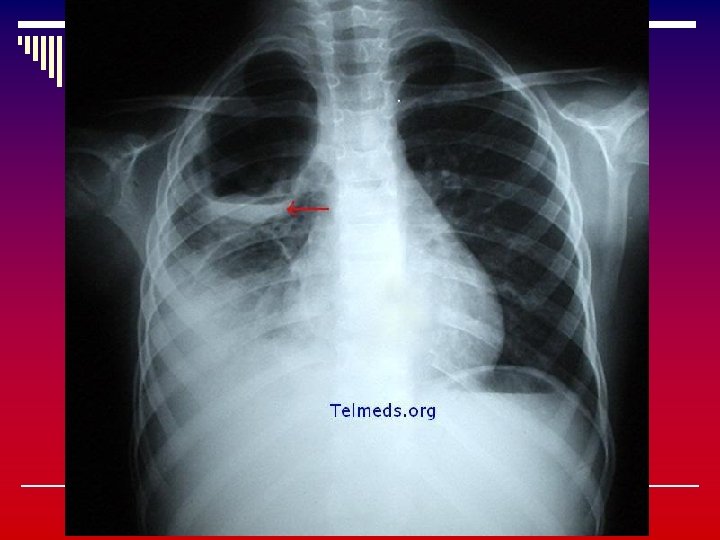

PNEUMONÍA STAPHILOCOCCUS AUREUS